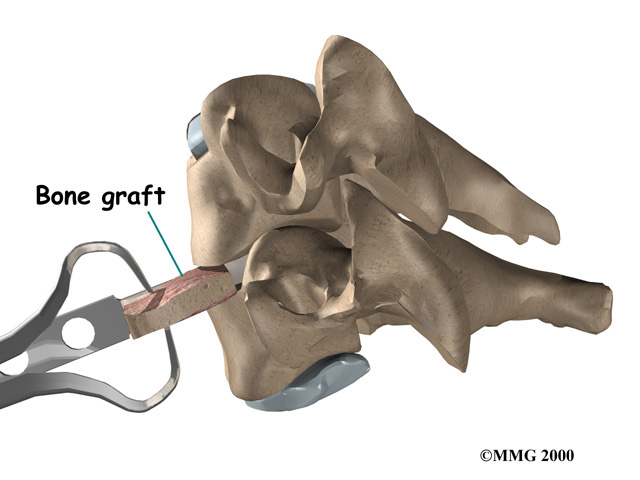

Cervical Fusion

A fusion surgery joins two or more bones into one solid bone. The purpose for doing spinal fusion is to increase the space between the vertebrae and to keep the sore joint from moving. This is usually done by placing a small block of bone graft in the space where a disc was removed. Opening up more space enlarges the neural foramen, takes pressure off the nerve roots, and eases tension on the facet joints. Cervical fusion is used to treat neck problems such as cervical radiculopathy, disc herniations, fractures, and spinal instability. There are two main types of fusion for neck problems.

- Anterior Discectomy and Fusion: Anterior discectomy and fusion is done through the front of the neck. After taking out the disc (discectomy), the disc space is filled with a small graft of bone. The bone is allowed to heal, fusing the two vertebrae into one solid bone.

Small Graft of Bone

The bone graft needs time to heal in order for the fusion to succeed. This requires the neck to be held still. After cervical fusion surgery, patients usually have to wear a special neck brace for several months. These neck braces are often bulky and restrictive. Recently, surgeons have begun using metal plates and screws (often referred to as instrumentation) to lock the bones in place. The instrumentation is fastened to the vertebrae, where it holds the bones still while the graft heals.